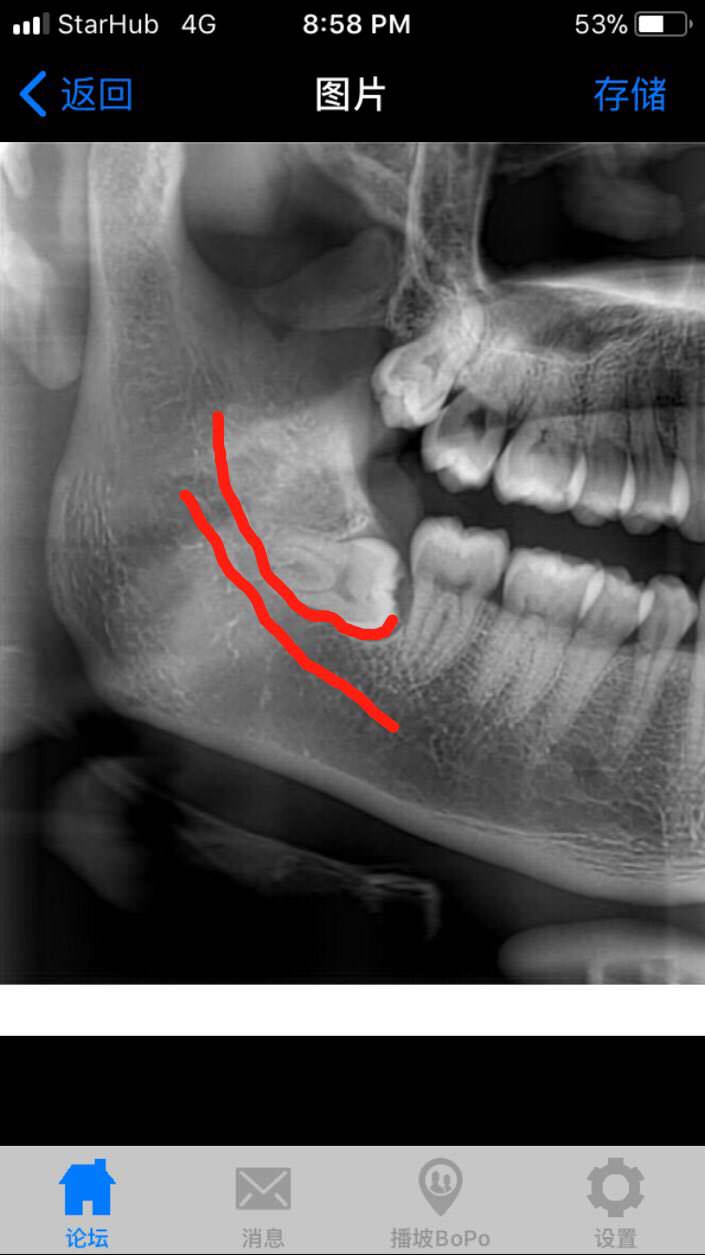

还是谨慎点 拔不好一辈子的事是不是上面那条神经已经被压的很多了

lz的跟我的一模一样啊横生,牙根勾神经。运气好的可以买toto…